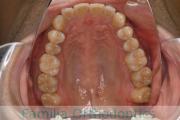

歯並びを綺麗にしたいということで来院されました。叢生(でこぼこ、凹凸、ガタガタ)と上下顎前突のため、上下左右から小臼歯を抜歯の上で、歯科矯正用アンカースクリューを併用したマルチブラケット法を行いました。約2年半、30回の通院が必要でした。

上下とも叢生がありますので、後戻りのリスクがあります。

上顎

下顎